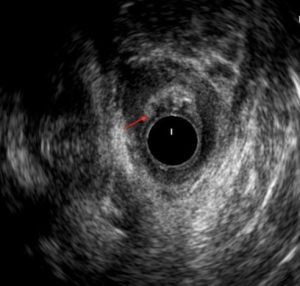

La analítica no refleja datos de infección y se realiza una ecografía endorrectal donde se objetiva una tumoración heteroecoica pararrectal derecha que se extiende hasta la rama derecha del puborrectal de 3,5×2,5 cm (ver imagen 1). Se completa estudio con resonancia magnética donde se informa una formación de 13×7,5×6,5 cm hiperintensa en T2 e hipointensa en T1 de borde lobulado y bien definido, con múltiples septos en su interior, en región pararrectal derecha ocupando la fosa isquiorrectal, con aparente comunicación con la pared lateral derecha del recto a las 8 horas a la altura del esfínter anal sin poder descartar etiología neoplásica (ver imagen 2), ni orientar más su posible naturaleza.

Imagen 1: Ecografía endorrectal: tumoración pararrectal derecha que se extiende hasta rama derecha del puborrectal de 3,5×2,5 cm.